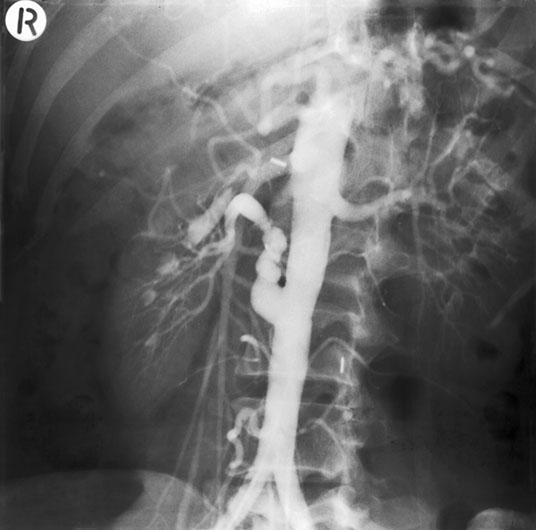

Fibromuscular dysplasia has a beaded appearance of narrowing and dilatation of the vessel wall and should be considered when a young patient presents with hypertension.

On the whole, fibromuscular dysplasia can be satisfactorily treated by balloon angioplasty. However, in this patient, it was not successful and surgical correction by a graft between abdominal aorta and renal artery was carried out.

However, the graft again stenosed as you can see. Fibromuscular dysplasia may affect many arteries and here the arrow is pointing to disease of the right common iliac artery in the same patient.